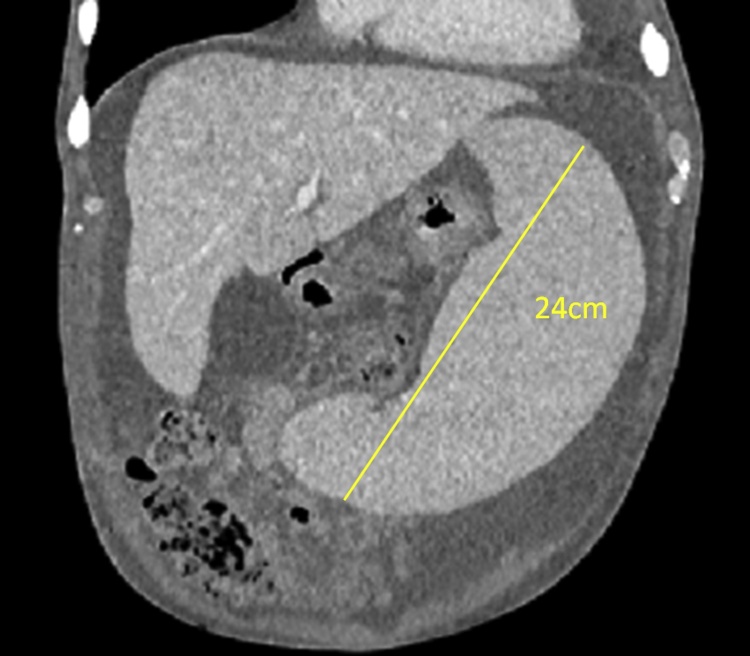

In June 2016, a 53 year-old man was admitted to our department to perform a planned splenectomy in idiopathic MF prior to ASCT. The patient had a significant past medical history of dilated cardiomyopathy diagnosed in 2014 after a severe episode of dyspnea with a residual left ventricular ejection fraction of 27%. New York Heart Association (NYHA) score was 3. American Society of Anesthesiologists (ASA) score was 3–4. ET was diagnosed about 25 years ago, confirmed with a bone marrow biopsy and treated with oncocarbide for 5 years. ET quicky evolved into idiopathic myelofibrosis coexisting with anemia which required weekly red blood cell transfusions. At the time of admission, abdominal examination showed a palpable spleen reaching the left iliac fossa and ascites. Declivous edemas were present as well. Laboratory tests revealed anemia (Hemoglobin: 9.8 g/dl); other routine exams including platelets, biochemical investigations and sierological viral markers were normal. Imaging evaluation including abdominal computerized tomography (CT) scan showed significant splenomegaly (diameters: 24 × 15 × 11 cm) and widespread and abundant ascites (Fig. 1).

Fig. 1.

CT SCAN: splenomegaly (24 cm of maximum diameter) and abundant ascites.